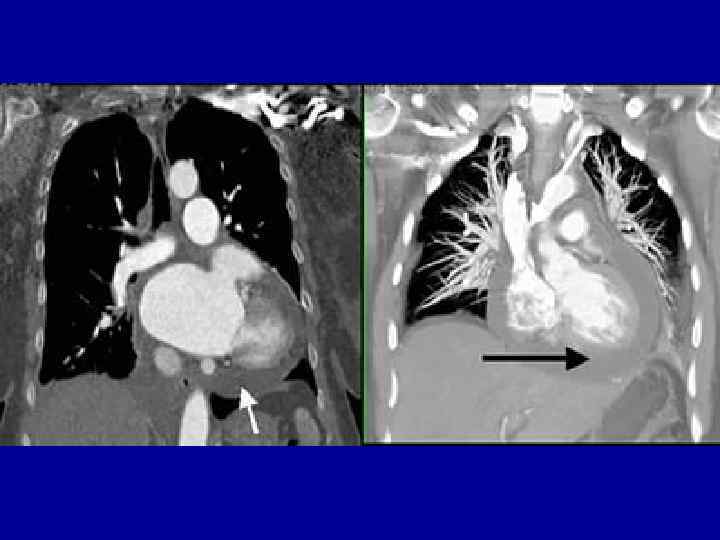

Инструментальные данные тампонады сердца: • ЭКГ – признаки: уменьшение амплитуды зубцов, высокие остроконечные зубцы Т в грудных отведениях либо картина, свойственная выпотным перикардитам • ЭХОКС: накопление жидкости в перикарде, наличие диастолического коллапса правого предсердия и правого желудочка; наличие дилатации нижней полой вены; • Рентгеновское исследование грудной клетки: cor «бутылка воды» , увеличение размеров сердца, сглаженность сердечных дуг, уменьшение амплитуды пульсации или полное ее исчезновение. • КТ сердца для выявления поражения перикарда

Диагностика хронических перикардитов • ЭКГ – подъем ST до 3 мес без формирования патологического Q; снижение вольтажа QRS • ЭХОКС – наличие жидкости в перикарде более 1, 0 см до 4, 0 см • R – графия легких ( конусообразная тень сердца), кальцинаты перикарда • Биохимия – показатели печеночной недостаточности

Рентгенологическое исследование • При хроническом течении экссудативного перикардита: наличие участков обызвествления в области перикардиальной тени и резкой очерченности линии ее контура. • Границы сердечной тени приобретают треугольную форму в отличие от шаровидной при остром выпотном перикардите.

Диагностика хронических форм перикардита • Набухание шейных вен на вдохе • В 30% - участки кальцификации перикарда • ЭХОКС – ненадежный метод выявления хронического перикардита • МРТ и КТ сердца выявляет утолщенные листки перикарда, спайки • Выравнивание внутриполостного давления в правом и левом желудочках • В отличие от тампонады способность к расслаблению сохраняется до половины диастолы